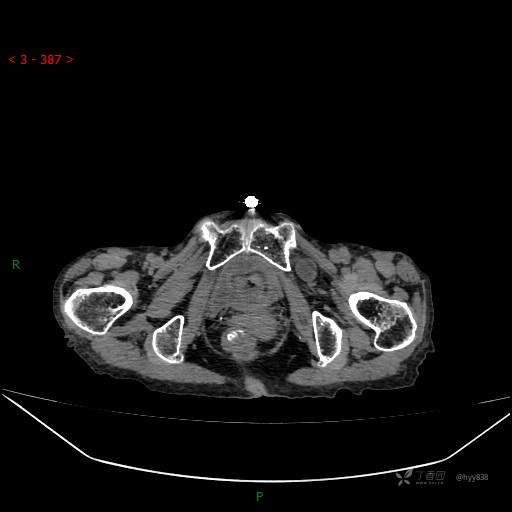

腹部CT平扫